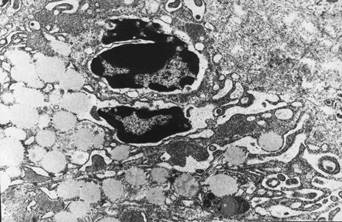

При гистолологическом исследовании тканей легких выявляются выраженные морфологические изменения с развитием признаков синдрома острого легочного повреждения. В альвеолах имеют место изменения по типу вентиляционно-циркуляторных расстройств. Они представлены более или менее обширными участками ателектаза и дистелектаза, чередующимися с участками вздутия легочной ткани. Просветы альвеол резко сужены и представляют собой узкие щели, в некоторых участках просвет альвеол не определяется. Рядом с такими зонами наблюдаются очаги резкого вздутия легочной ткани, проявляющиеся расширением просвета альвеол и истончением межальвеолярных перегородок, вплоть до их разрыва, обеднением клеточными элементами. Просветы терминальных и респираторных бронхиол резко расширены. В просветах альвеол – отечная жидкость, эритроциты, десквамированные альвеолоциты. Отек затрагивает практически все компоненты аэрогематического барьера. Так, в эндотелиоцитах капилляров межальвеолярных перегородок он проявляется в резком разрыхлении и разрежении цитоплазмы, что сопровождается снижением ее электроннооптической плотности. В цитоплазме появляются сливающиеся между собой микропиноцитозные везикулы, в результате чего образуются различные по размерам и форме вакуоли. В ядрах, имеющих, как правило, округлую и/или овальную форму, наблюдается перераспределение хроматина с его преимущественной локализацией в виде глыбок вблизи кариолеммы, из-за чего центральная часть ядра просветляется и разрыхляется. В этих условиях эндотелиальные клетки увеличиваются в размерах, что приводит к сужению просвета капилляров. Базальные эндотелиальная и эпителиальная мембраны теряют четкость своих контуров и выглядят разрыхленными, а не гомогенными. Интерстиций расширяется, само интерстициальное пространство приобретает светлый вид низкой электроннооптической плотности с разрыхленными обрывками коллагеновых волокон. Среди альвеолоцитов в наибольшей степени изменяются альвеолоциты I типа. При этом наиболее выраженные их изменения отмечаются в цитоплазматических отростках. В цитоплазме появляется большое количество хаотично расположенных микропиноцитозных везикул, многие из которых сливаются между собой с образованием более или менее крупных вакуолей. Также имеет место дегрануляция тканевых базофилов, с «запустением» секреторных гранул (рис. 2). Нарушения микроциркуляции сопровождаются развитием резкого повышения проницаемости сосудистой стенки с развитием диффузной геморрагической инфильтрацией в межальвеолярных перегородках и выраженным интерстициальным отеком.

Рис. 2. Легкое крысы при моделировании реперфузионного синдрома через 12 часов после снятия жгутов. Дегрануляция базофила с «запустением» секреторных гранул. Электронная микрофотография. Ув. 8000.